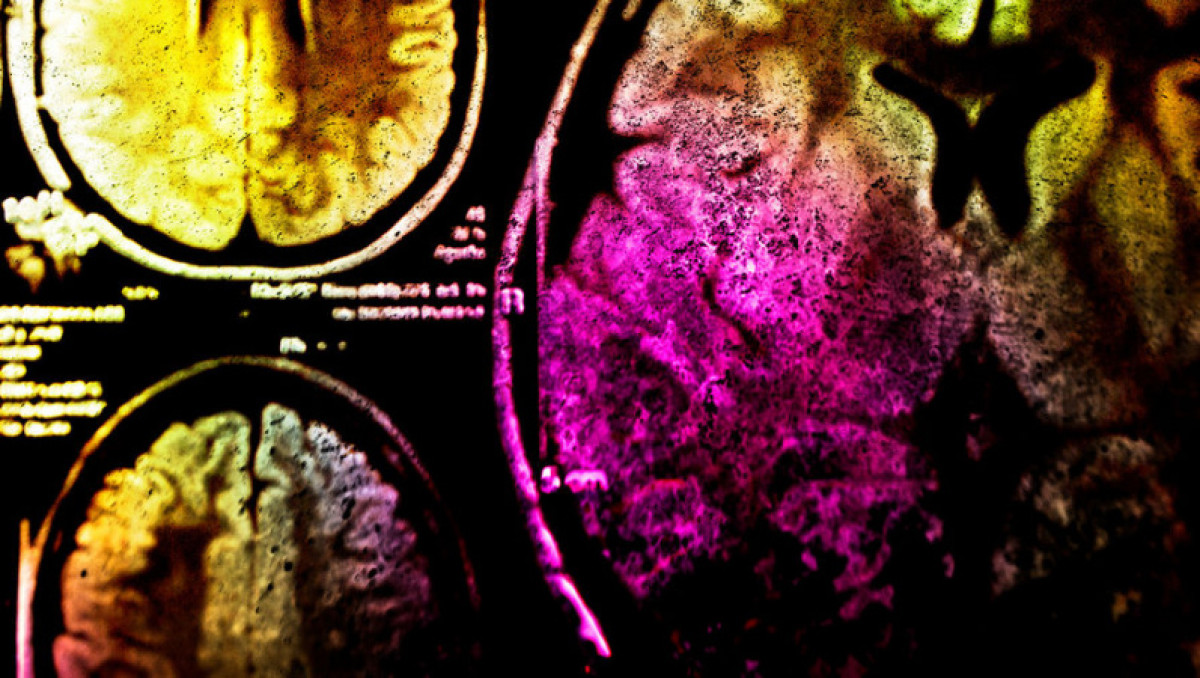

Канадские врачи столкнулись с неизвестной болезнью, которая вызывает потерю памяти, галлюцинации и атрофию мышц, сообщает The Guardian.

"Необычное заболевание выявили у 43 жителей провинции Нью-Брансуик. Местные жители узнали о болезни после того, как в прессе появились материалы Агентства общественного здравоохранения. В них говорилось о симптомах, похожих на проявления болезни Крейтцфельдта-Якоба. Это редкое смертельное заболевание мозга", - отмечается в сообщении.

Как уточняется, в данный момент исследователи пытаются понять, имеют ли они дело с не встречавшейся ранее болезнью или с похожими симптомами разных, не связанных друг с другом заболеваний.

Пока что известно, что все больные жаловались на боли неизвестного происхождения, спазмы и изменения поведения. В течение полутора-двух с половиной лет у людей появлялись когнитивные нарушения, истощение мышц, повышенное слюноотделение и стук зубов.

Кто-то даже отмечал у себя галлюцинации – например, ощущение, будто по коже ползают насекомые.

Эксперты отмечают, что в 2015 году был выявлен один такой случай, а в 2019-м их было уже 11. В прошлом году их число возросло до 24.

"У нас нет доказательств, позволяющих предположить, что это прионное (связанное с инфекционными белками, прионами) заболевание. Мы не знаем, что его вызывает. Сейчас у нас есть только вновь появляющиеся пациенты с этим синдромом", – рассказал руководитель исследования, невролог Алиер Марреро.

"За последние 20 с лишним лет мы не видели такого кластера устойчивых к диагностике неврологических заболеваний, как этот", – добавил глава канадской сети эпиднадзора CJD Майкл Култхарт.